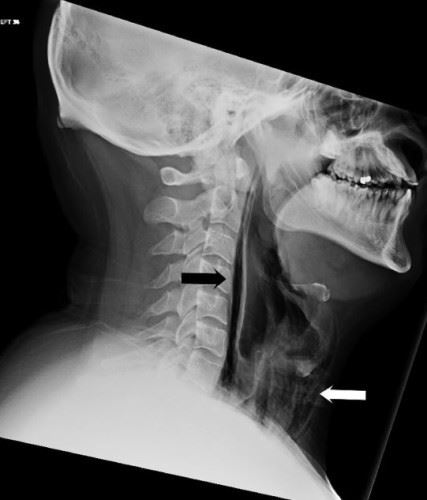

Sekiranya anda dengan sengaja menghentikan bersin secara tiba-tiba, tekanan tersebut akan dialihkan kepada bahagian tubuh lain seperti telinga yang membolehkan gegendang telinga retak sekaligus boleh menjejaskan pendengaran anda.

Bukan itu sahaja, tekanan udara yang terperangkap itu akan mengakibatkan kerosakan pada mata disebabkan pembuluh darah dalam mata terluka. Lebih teruk, leher serta diaphgram juga boleh terluka. Kejadian ini jarang berlaku tetapi ia mampu juga menyebabkan strok.